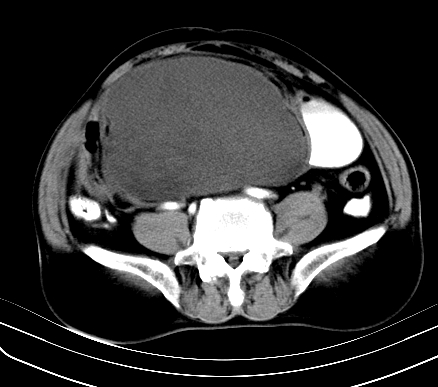

标题: CT19729B:男,74岁,因腿疼就诊,查体触腹部肿物,

增强扫描

动脉期

【ct表现】

1、肿块巨大,往往位于腹膜后,长大后才引起症状而就诊;那么位于腹膜后的肿瘤80%为恶性肿瘤。

2、实性肿瘤,增强扫描轻度不均强化,实性肿瘤一般不是好东西。

3、肿瘤边缘似见少许脂肪样密度。

4、腹膜后未见肿大淋巴结,但肿瘤于临近的肠管及组织接触紧密。

【诊断】

腹部占位,考虑位于腹膜后的恶性肿瘤,脂肪肉瘤(实体型)可能性大。

术后病理结果:腹膜后脂肪肉瘤。